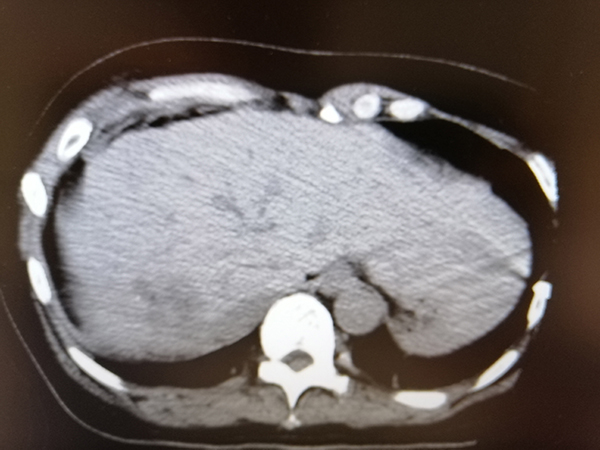

卢女士不幸罹患结肠癌,手术切除后再次发生肝内转移,经多程化疗后肿瘤明显缩小,但肿瘤靠近血管,手术切除风险大且费用较高。2020年10月28日下午,在肿瘤科主任鲁培博士的带领及李竟长副主任医师的积极协调下,肿瘤科介入团队郭旭飞副主任医师和石周主治医师经过反复讨论,并与病人深入沟通后,最终制定了肝转移瘤射频消融术的治疗方案。历时1小时,手术顺利完成,患者取得良好的治疗效果。

治疗中